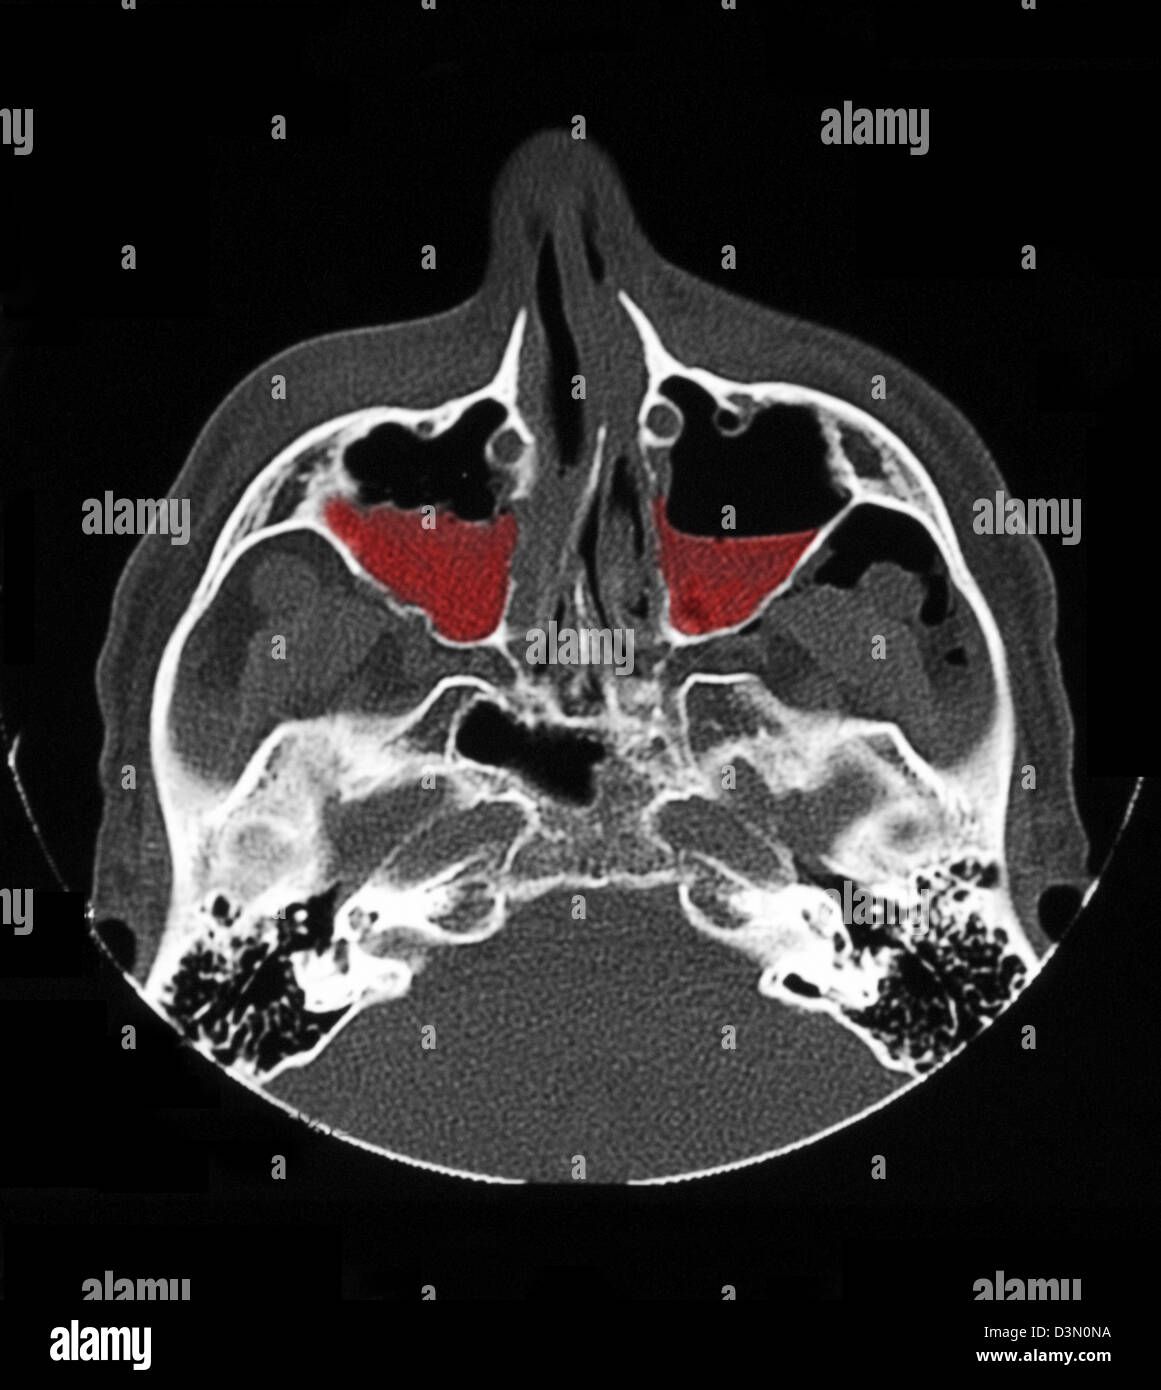

CT scan image showing bilateral maxillary sinus fractures Stock Photo Maxillary Sinus Osteoma Ct As in our study, literature reports a majority of. computed tomography (ct) of the head and paranasal sinuses was performed, which revealed a solitary exophytic osseous. to assess the maxillary sinus ostium (mso) dimension and measuring the distance to nearby anatomical structures. routine cts are said to reveal approximately 1% of osteomas [1], [2]. ct scan. Maxillary Sinus Osteoma Ct.

Maxillary Sinus Osteoma Ct . As in our study, literature reports a majority of. ct scan showing an osteoma and mucosal thickening in the right maxillary antrum and polypoidal mass in the left. to assess the maxillary sinus ostium (mso) dimension and measuring the distance to nearby anatomical structures. routine cts are said to reveal approximately 1% of osteomas [1], [2]. surgical excision represents the unequivocal treatment modality for symptomatic paranasal sinus osteomas. computed tomography (ct) of the head and paranasal sinuses was performed, which revealed a solitary exophytic osseous. ct scan revealed a pedunculated bony mass arising from the lateral wall of the maxillary antrum (fig. ct scan showing the incidental finding of a small osteoma located in the floor of the left maxillary sinus.